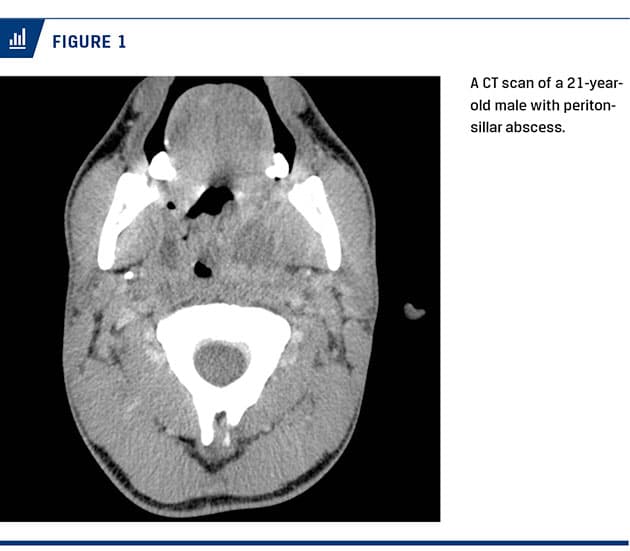

Patients with PTA (Figure 1) underwent either acute tonsillectomy (n = 1,435) or incision and drainage (n = 185). In addition, eleven patients had no surgical intervention (two patients refused surgery and nine patients had spontaneous perforation). In patients undergoing acute tonsillectomy, 1,016 (71%) patients were treated with penicillin (in combination with metronidazole in 396 of the cases), no antibiotics were given to 404 (28%) patients, and 15 (1.0%) patients were prescribed more broad-spectrum antibiotics. 99% of PTA patients undergoing incision and drainage were treated with penicillin, either as monotherapy (n = 111) or in combination with metronidazole (n = 72).